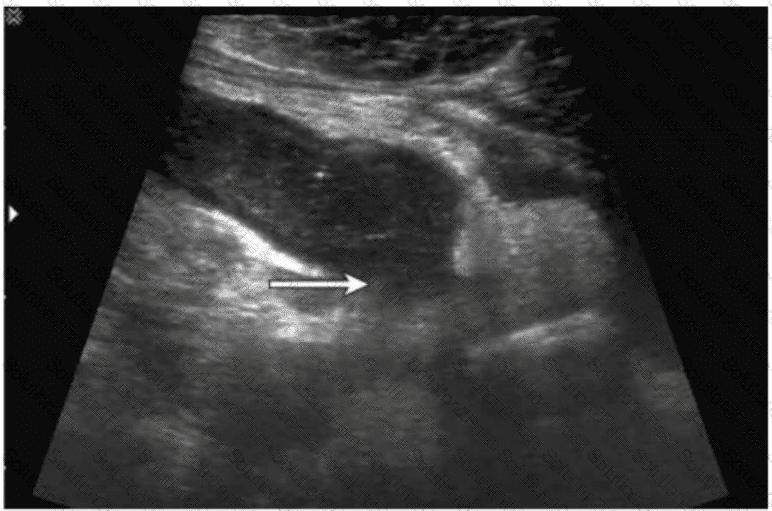

A patient presents with right lower quadrant pain and fever. Which condition is most likely indicated by the arrow on this image?